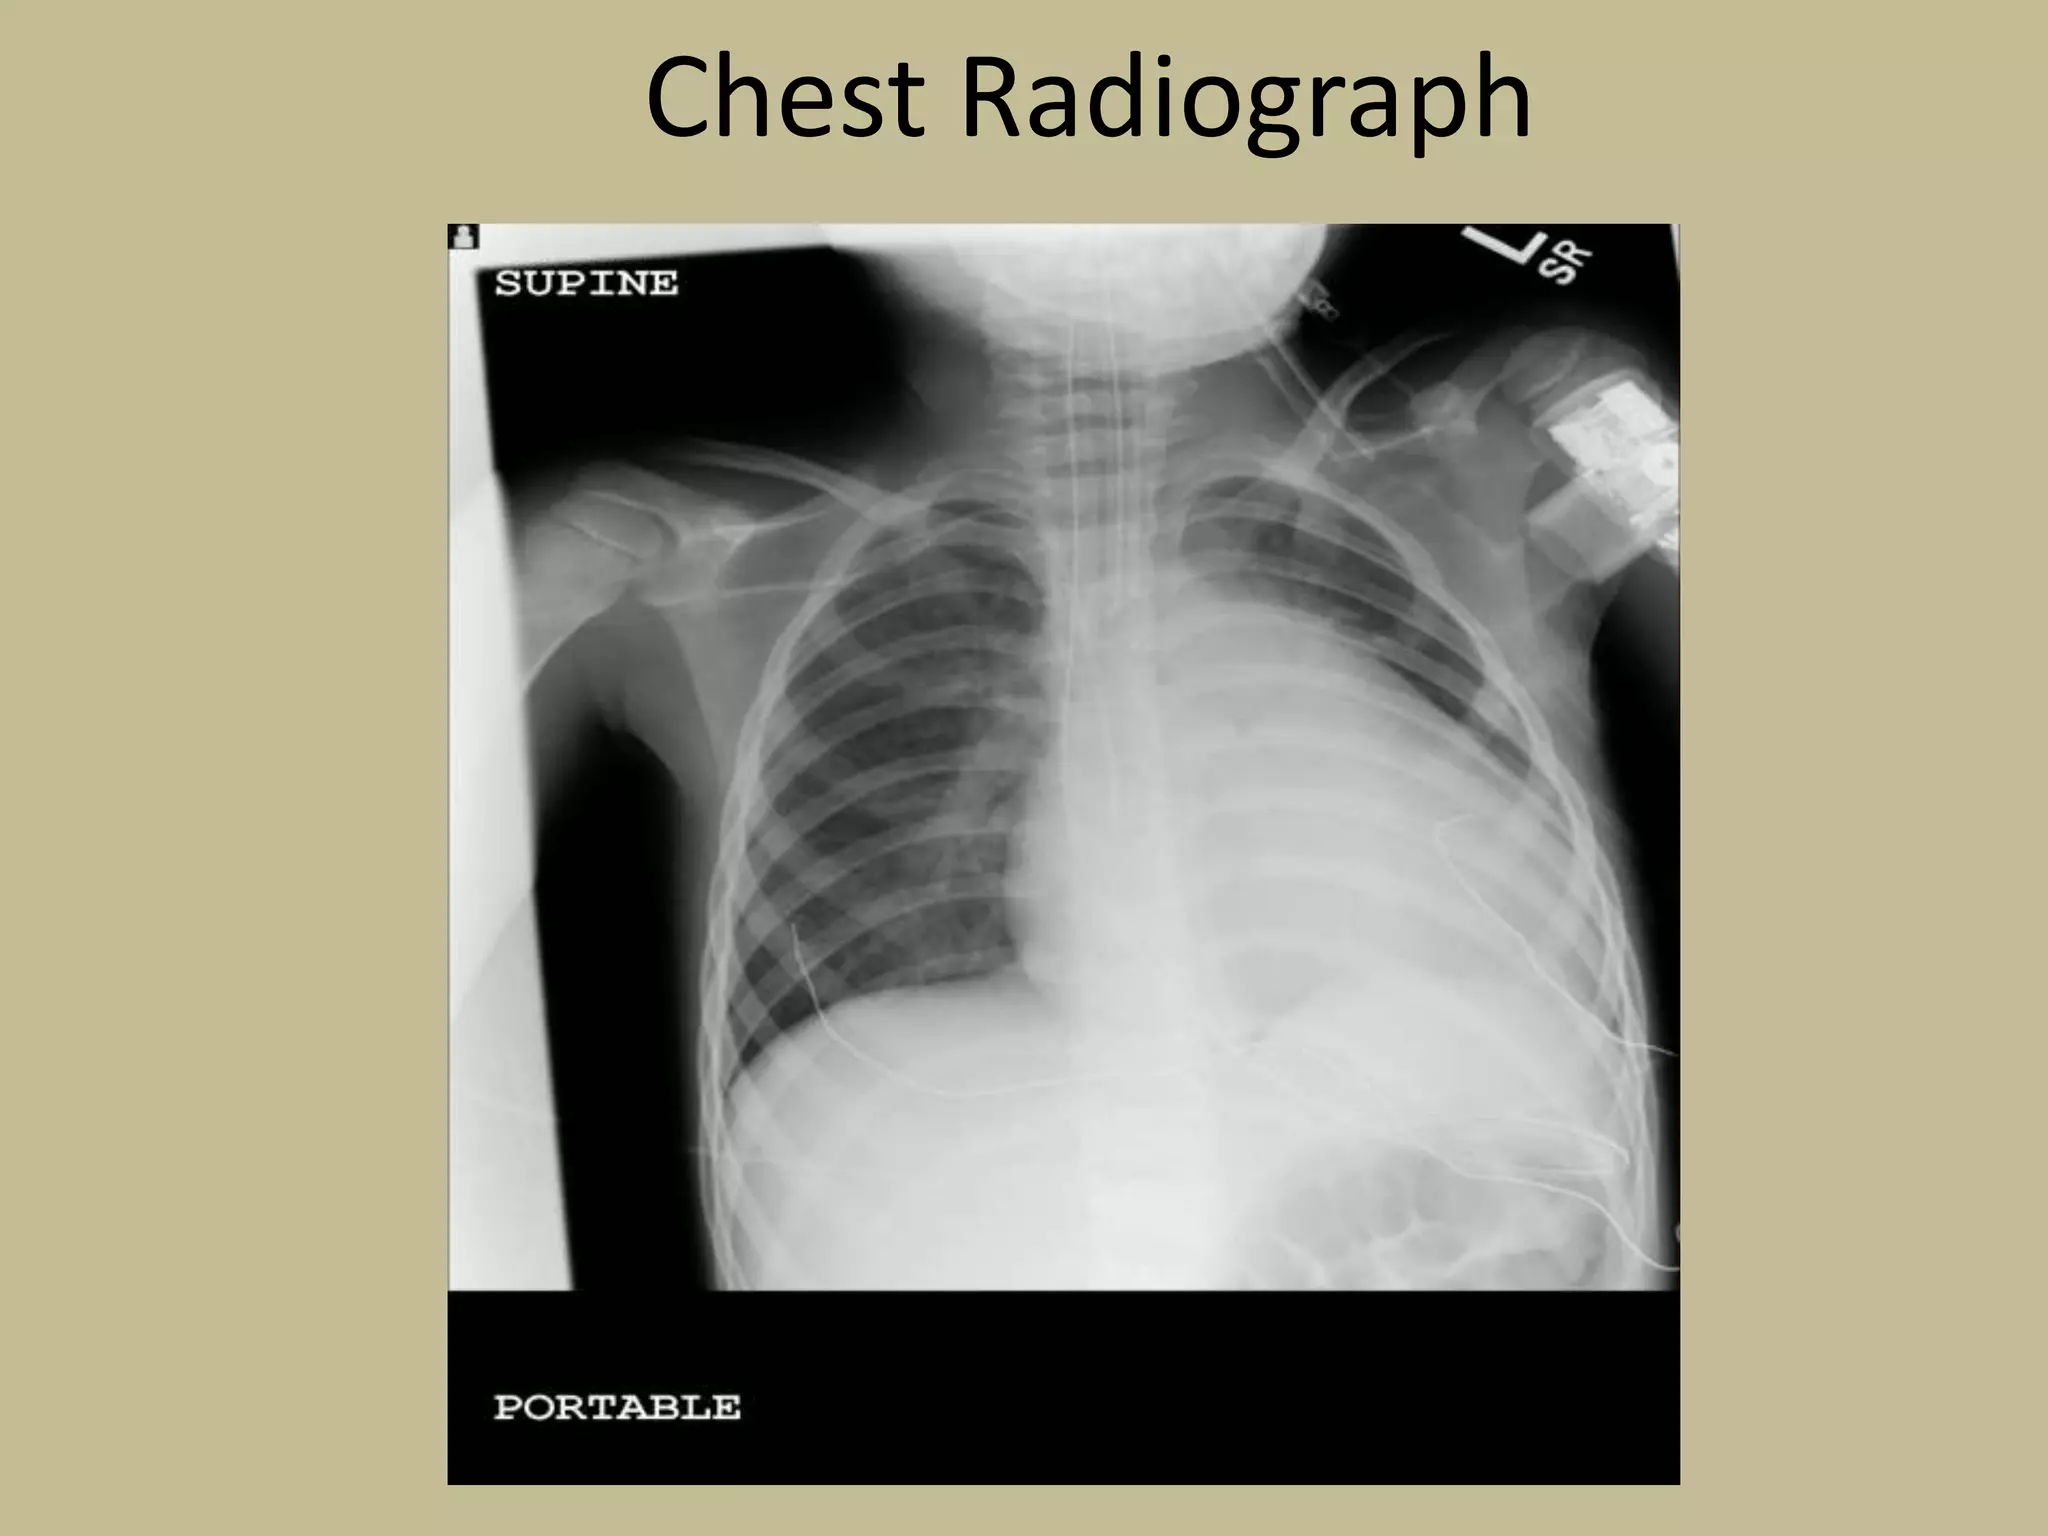

Chest Radiograph

Chest X-Ray- Variable (Normal to Cardiomegaly)